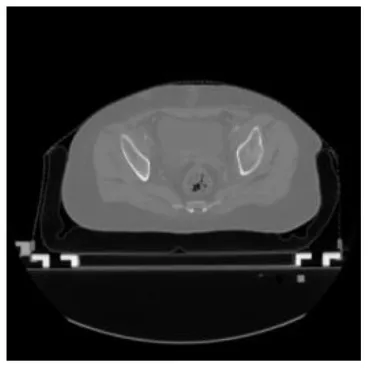

According to the acquired model parameters mentioned above, the testing set was calculated and examined. The performance of the modified algorithm for automatic organ segmentation in CT images is shown in Table 1. The organ contours segmented automatically by the algorithm were similar to those delineated by physicians manually. The model parameters including DSC, Accuracy, Recall, and Precision evaluation ones were served to evaluate the segmentation effectiveness of each organ in the validation and testing sets. In our work, the BCDU-Net CNN algorithm model was used to automatically segment different organs with the different training parameters such as epoch learning rate. The CT images which were randomly selected from the patients were put into the network model for training, and then the contours of different organs which were delineated automatically by the AI technology and manually by medical doctors were evaluated with the similarity coefficients, respectively. The results are given in Table 2. Most of the DSC values were better than 0.85 and among them the best even reached up to 0.9676. Generally, the automatic segmentation results met the requirements of clinical practice.

| Input CT image | Organs with manual segmentation | Organ with automatic segmentation | |

| Bladder | ![]() | ![]() | ![]() |

| Brainstem | ![]() | ![]() | ![]() |

| Eye-L | ![]() | ![]() | ![]() |

| Eye-R | ![]() | ![]() | ![]() |

| Femur-L | ![]() | ![]() | ![]() |

| Femur-R | ![]() | ![]() | ![]() |

| Heart | ![]() | ![]() | ![]() |

| Intestine | ![]() | ![]() | ![]() |

| Kidney-L | ![]() | ![]() | ![]() |

| Kidney-R | ![]() | ![]() | ![]() |

| Liver | ![]() | ![]() | ![]() |

| Lung-L | ![]() | ![]() | ![]() |

| Lung-R | ![]() | ![]() | ![]() |

| Mandible | ![]() | ![]() | ![]() |

| Rectum | ![]() | ![]() | ![]() |

| Spleen | ![]() | ![]() | ![]() |

| Stomach | ![]() | ![]() | ![]() |

The result of manual and automatic organ segmentation.